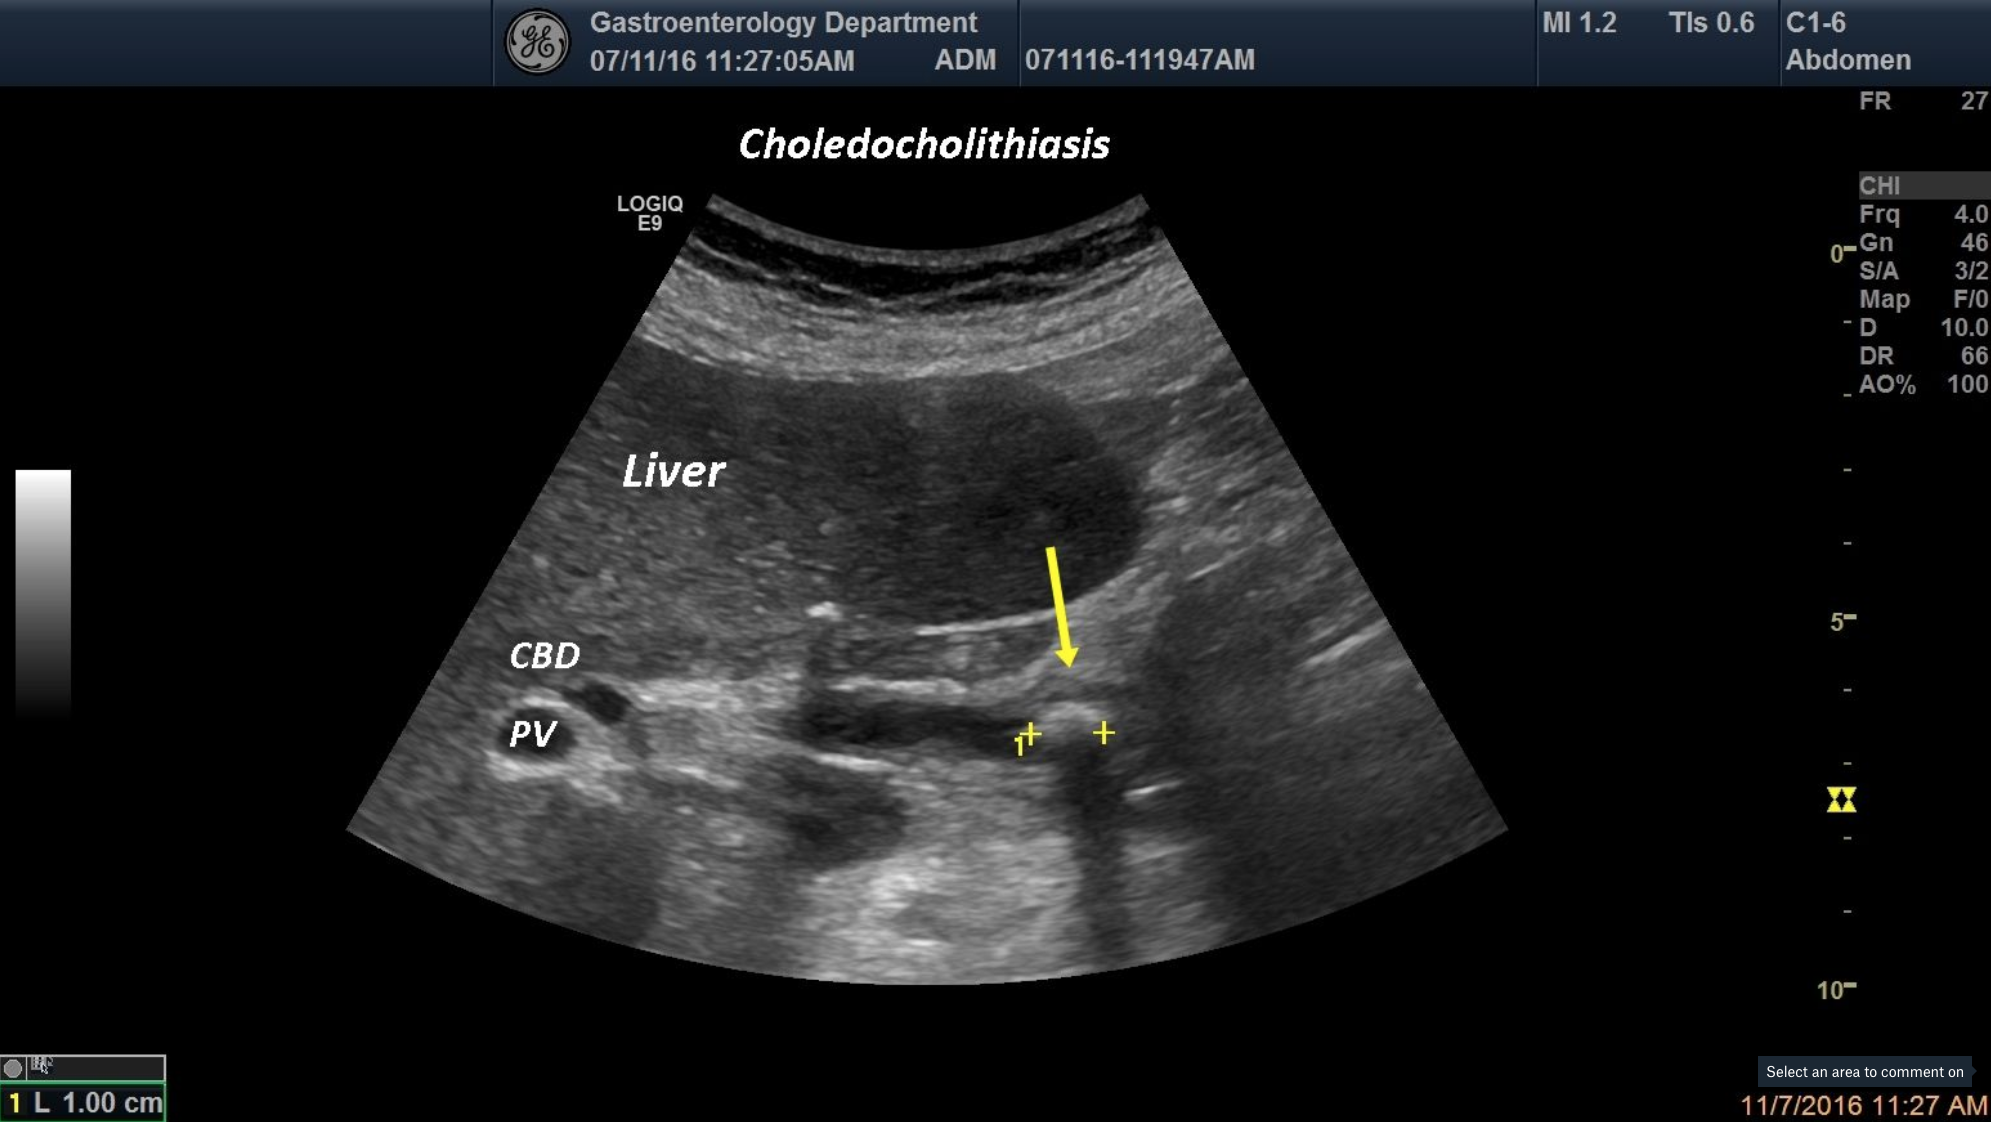

A 59-year-old patient was admitted in our department for jaundice and epigastric-colicky pain. During ultrasound examination we depicted an hyperechoic structure inside the common bile duct and an enlarged CBD.

![Choeledocholithiasis [1 image]](http://s834315022.websitehome.co.uk/wp-content/uploads/2021/01/Screen-Shot-2021-01-05-at-12.30.06.png)